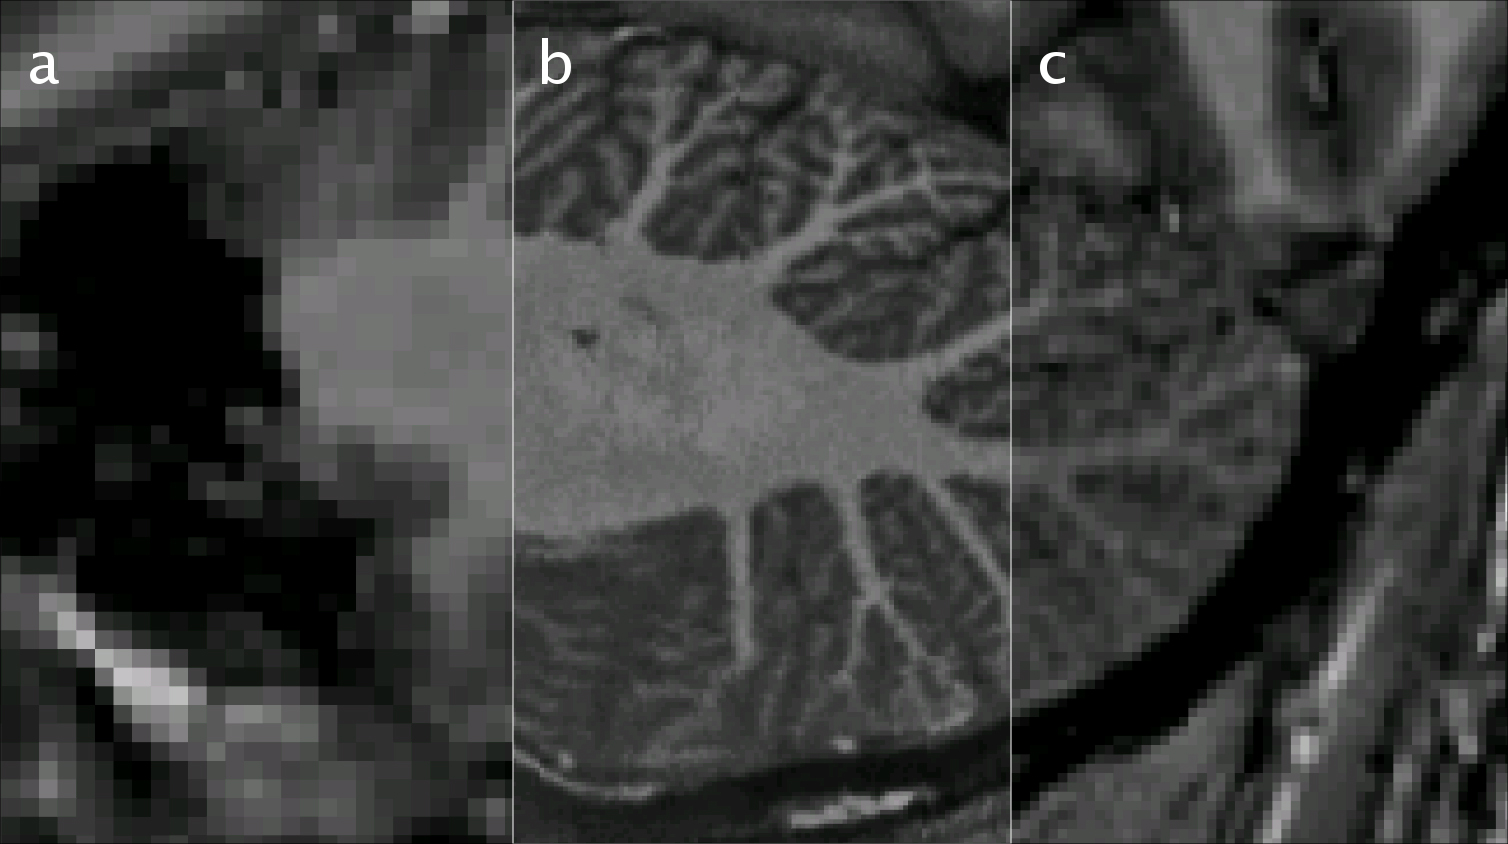

Illustration einer MRT-Aufnahme des Kleinhirns. Links (a) mit neurowissenschaftlicher Standardauflösung von 1 mm, in der Mitte (b) mit der höchsten erreichten Auflösung von 0,25 mm und rechts (c) mit einer Auflösung von 0,5 mm, welche derzeit als „high end“ bezeichnet wird. Die Abbildung zeigt nur einen kleinen Ausschnitt aus dem veröffentlichten Datensatz, welcher den gesamten Kopf in einer bisher einzigartig hohen Auflösung darstellt. (Bild: Falk Lüsebrink/Universität Magdeburg

Bild 1 // Quelle: Falk Lüsebrink/Universität Magdeburg // Bildunterschrift: Illustration einer MRT-Aufnahme des Kleinhirns. Links (a) mit neurowissenschaftlicher Standardauflösung von 1 mm, in der Mitte (b) mit der höchsten erreichten Auflösung von 0,25 mm und rechts (c) mit einer Auflösung von 0,5 mm, welche derzeit als „high end“ bezeichnet wird. Die Abbildung zeigt nur einen kleinen Ausschnitt aus dem veröffentlichten Datensatz, welcher den gesamten Kopf in einer bisher einzigartig hohen Auflösung darstellt.